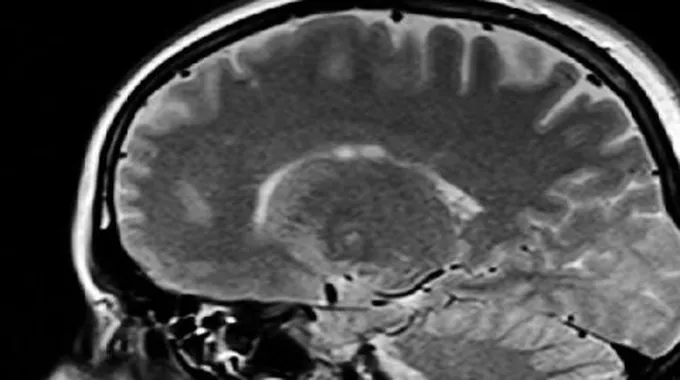

يُعتبر تشخيص نزيف المخّ صعباً ما لم يرتبط بظهور علامات تدلّ عليه، إذ يلجأ المختصّون لإجراء عدد من الفحوصات في حال ظهور بعض العلامات على المريض كفقدان الإحساس، وصعوبة الكلام، أو عند الاشتباه بوجود جلطة دماغية، ومن أبرز هذه الفحوصات ما يأتي:[1][3]

- التصوير الطبقي المحوري (بالإنجليزية: Computed topography).

- التصوير بالرنين المغناطيسي (بالإنجليزية: Magnetic resonance imaging).